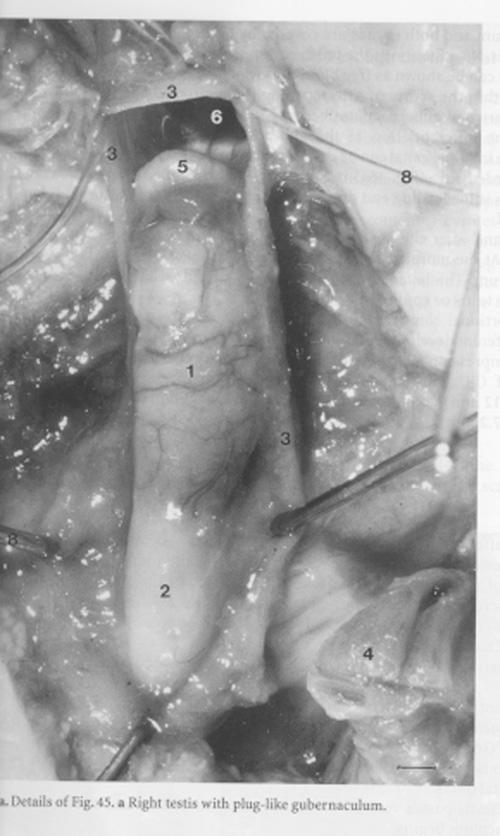

Anhand der Untersuchungen konnten sie den bisher umstrittenen inneren Abstieg der Sexualorgane vor dem Austritt der Hoden in den Hodensack beim Menschen beweisen: Die Anlage für die Eierstöcke und die Hoden steigen gleichermaßen herab, beim weiblichen Embryo erreichen die Ovarien ihre Position schon recht früh. Das Schicksal des Gubernaculum Hunteri teilten die Forscher in fünf Phasen ein, von seiner Entstehung in der ersten, über sein starkes Wachstum in der zweiten Phase, erste sexuell unterschiedliche Entwicklungen in der dritten Phase bis hin zu seinem Weg in den Hodensack, wohin es die Hoden begleitet. In keiner der Phasen verbindet das Leitband die Hoden mit dem Boden des Hodensacks; daraus folgt, dass die Hoden nicht - wie früher angenommen - durch eine Verkürzung des gummibandähnlichen Gubernaculum in den Hodensack hineingezogen werden können. Das Gubernaculum hat demnach verschiedene Funktionen, z. B. weitet es durch seine Verdickung besonders im 7. Lebensmonat des Fötus den Leistenkanal, durch den die Hoden schließlich den Unterleib verlassen.

K.J. Barteczko, M.I. Jacob: The Testicular Descent in Human. Origin, Development and Fate of the Gubernaculum Hunteri, Processus Vaginalis Peritonei, and Gonadal Ligaments. (= Advances in Anatomy, Embryology and Cell Biology 156) Berlin, Heidelberg, New York, Springer 2000, ISBN 3-540-67315-6